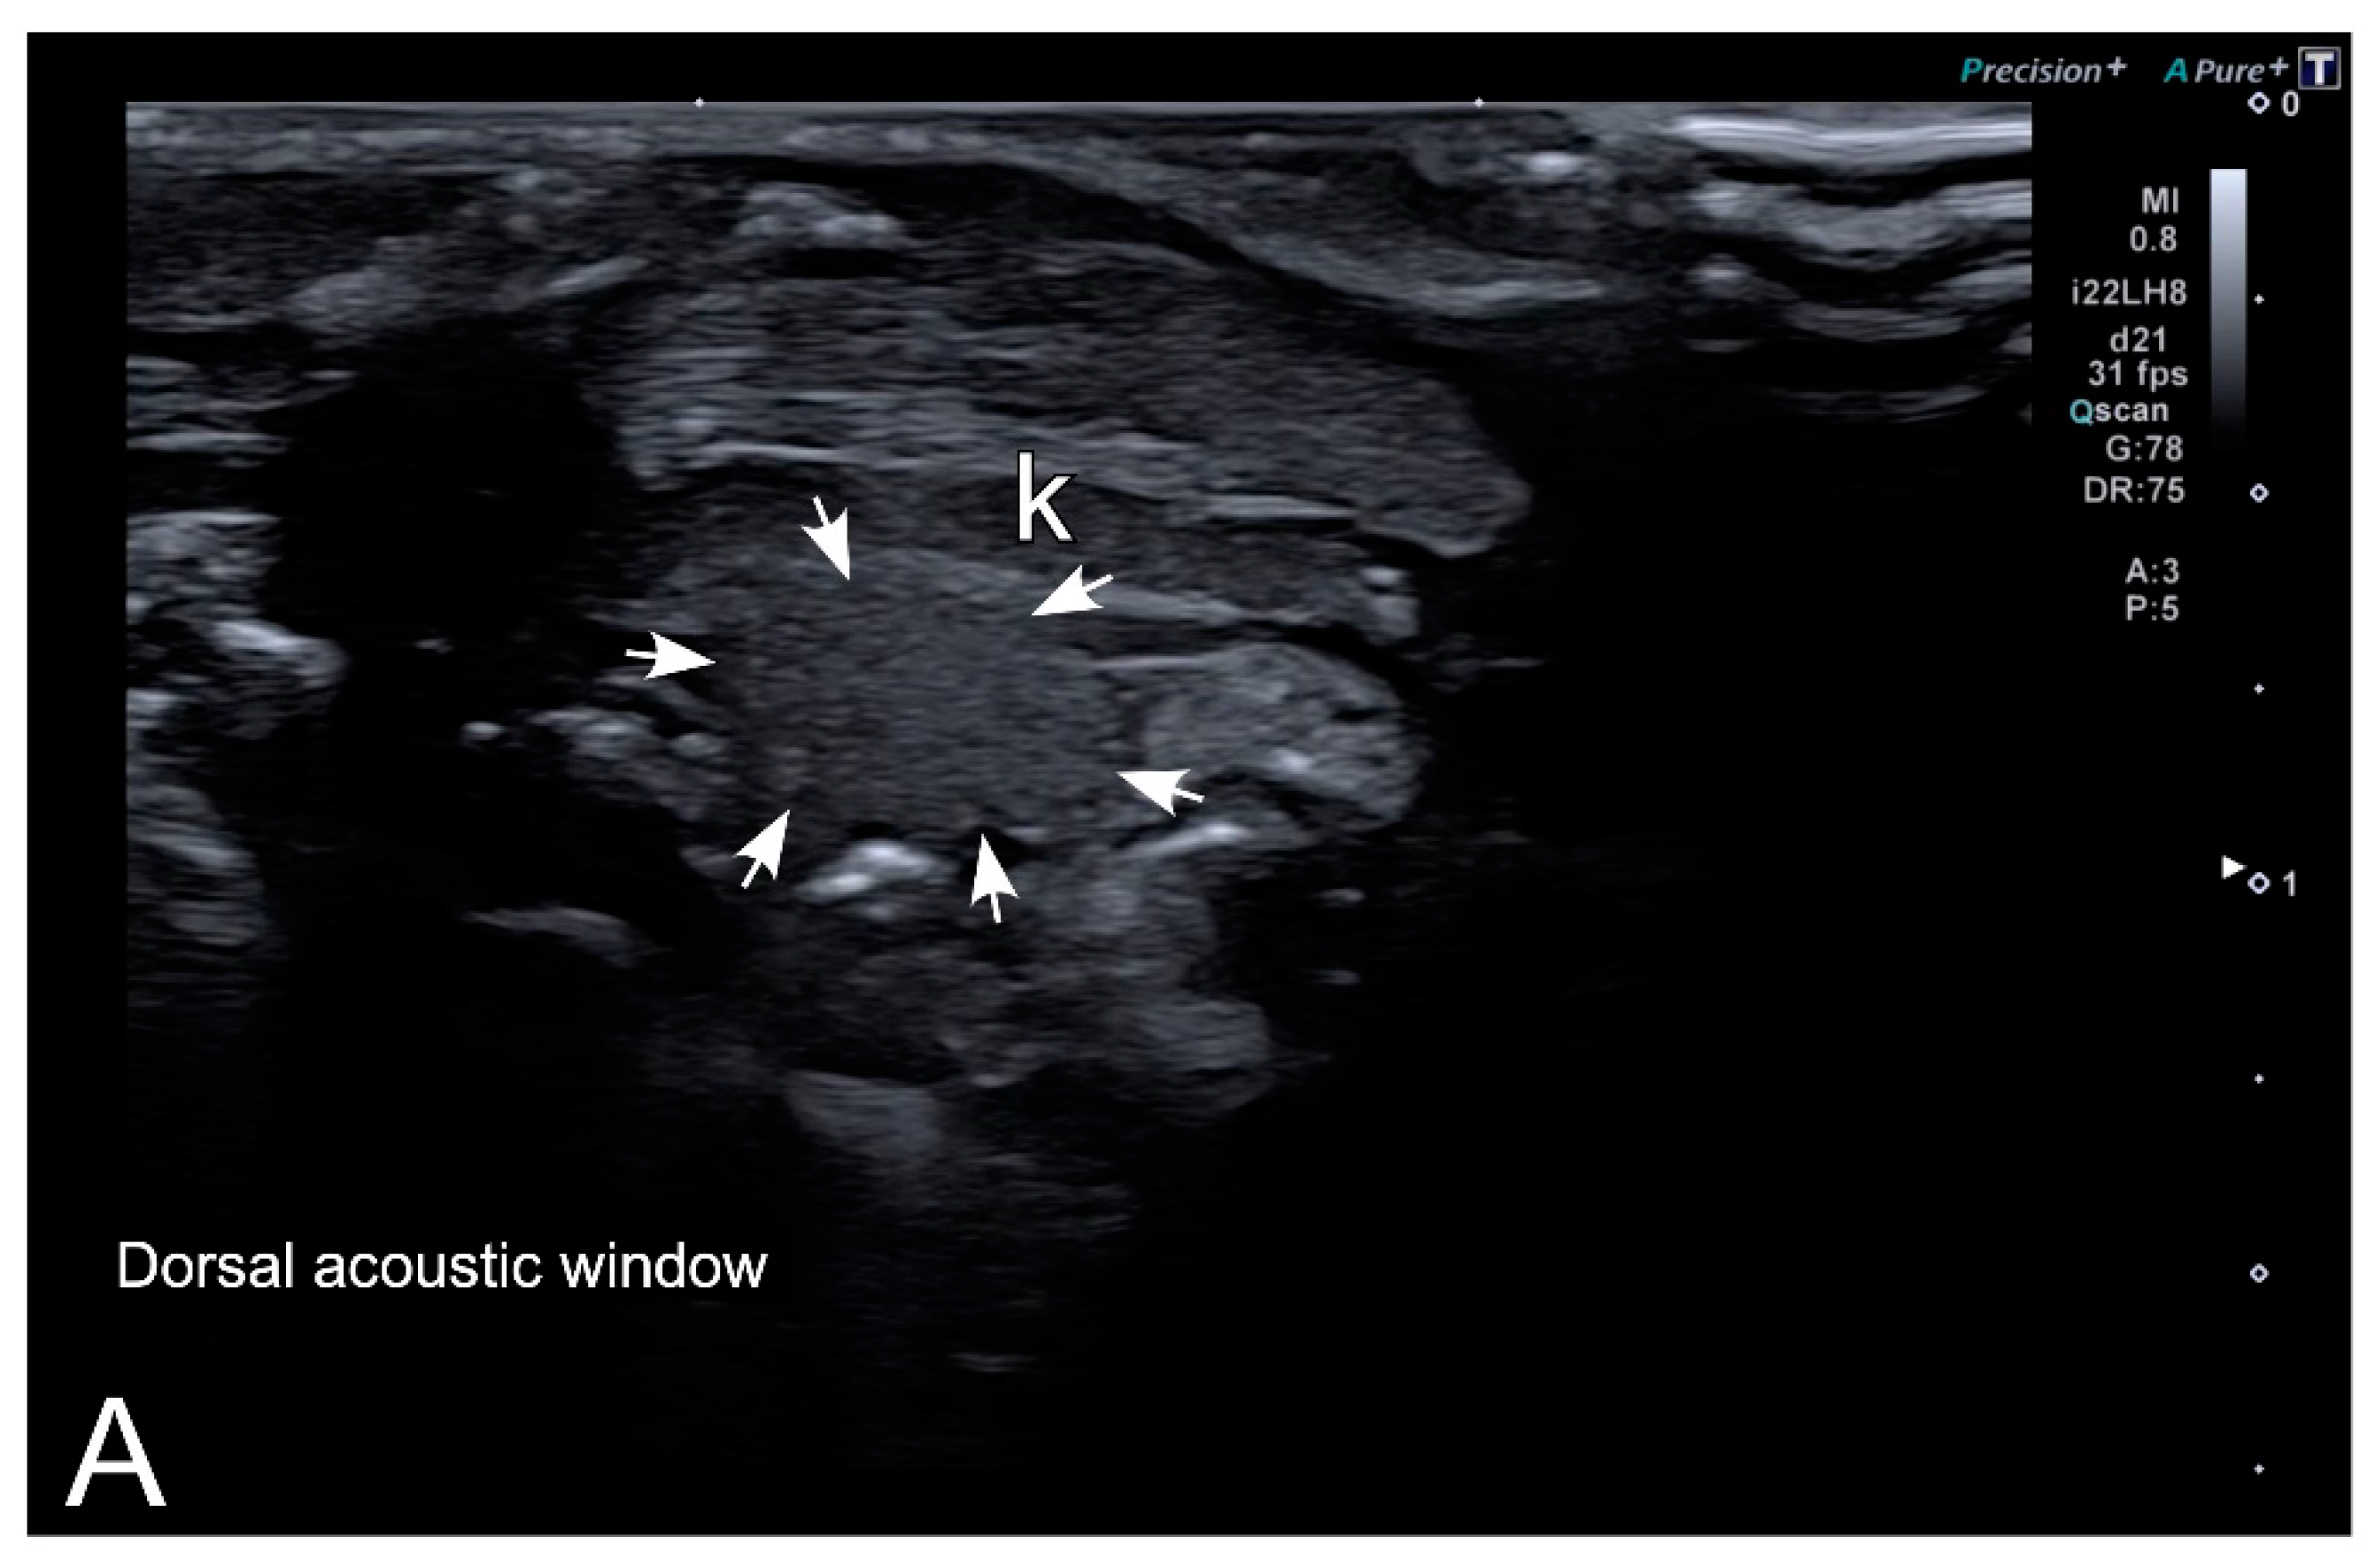

3.2. Ultrasonography